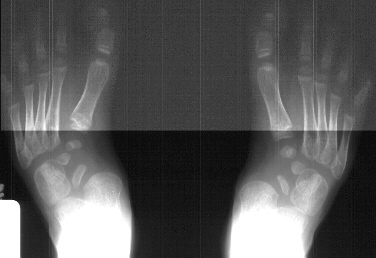

treated with casts or splints. On examination he has a short thick foot

with a kidney bean shaped curve to its lateral border. The arch is not

high but has a heavy callus bilaterally. The following bilateral foot deformities

were also present on physical examination: hindfoot valgus of approx. 20-30

degrees, metatarsus adductus, and prominence of the talar head in the medial

arch with thickened callus over the bony prominence.

To

make the diagnosis of skewfoot, the first metatarsal angle to the talus

on an AP x-ray has to be greater than 30 degrees.